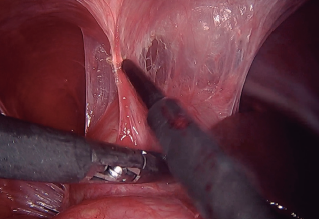

Imágenes y Cirugía

Valdemir José Alegre Salles, Gabriela Teles Cortez, Isabela Simões de Araujo Alegre Salles, Isabele Teles Cortez, Vitória Coutinho Ribeiro